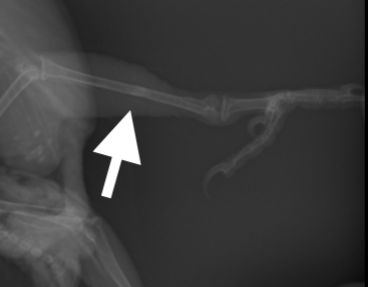

レントゲンを撮影すると頸足根骨がほぼ中央で骨折していることがわかりました。

骨折の部位、経過時間、本人の状態も手術可能な状態でしたので、ピンニング術を行うことにしました。

骨折部位の皮膚を最小限切開し、骨折部位を露出し、まずは遠位端(趾の方)にピンを挿入し、踵部の関節までピンを貫通させます。その後近位端にピンを挿入し、膝の関節は貫通しないように、長さを確認しながら、ピンを調節します。